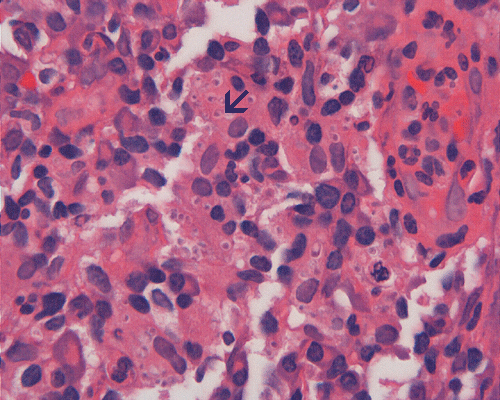

On low-magnification, the biopsy appears to be a piece of colonic mucosa without evidence of necrosis, erosion, or ulcer (Panel A). On medium-magnification, the lamina contains some vaguely formed collections of large cells (Ú in Panel B). On high-magnification, there are many large, round cells with eccentric nuclei. These are macrophages in clusters that are consistent with granulomas.  Many small, grayish to basophilic, vesicle-like structures are present in the cytoplasm (Panel in C). In other areas, these large, round cells do not really form small clusters and are admixed with lymphocytes (Panel D). Again, many small, grayish vesicle-like structures are present in these cells. A grayish to basophilic core is present and is surrounded by halo (Ú in Panel E).  These structures are most suggestive of microorganisms particularly fungus. On periodic acid Schiff (PAS), these vesicles appear bright purple-red (Panel F and G). The basophilic core is also strongly positive for PAS stain (Panel G). These microorganisms appear dark with Gomori methamine silver stain (Panel H and I).

In immunocomprised patients that have defective cellular immunity, granuloma formation may be rather indistinct as illustrated in our case. The yeast form of Histoplasma capsulatum is found in tissue and they are usually under 5 mm in diameter and appear as ovoid yeasts.  The lung is the most affected organ. Granuloma formation, typically multiple, with extensive caseous necrosis and a variable amount of calcifications are the typical pathologic changes in the lung. These granulomas are often demarcted from the surrounding tissue by a fibrous wall. Granulomas in the lung can get quite calcified with time. The pulmonary nodules can also enlarge slowly to give a wrongful clinical impression of neoplasm, the so-called histoplasmoma. The living yeast in tissue, often occur in clusters, has a basophilic center and a translucent halo that represents the capsule. They are often engulfed by histiocytes as illustrated in this case. Dead organisms appear eosinophilic and cannot be detected easily in granuloma by hematoxylinj-eosin stain. The microorganism is numerous and can be identified on routine hematoxylin-eosin stain with astute observation and high index of suspicion. Typically, there are numerous yeasts and they are present even in heavily calcified nodules or granulomas.